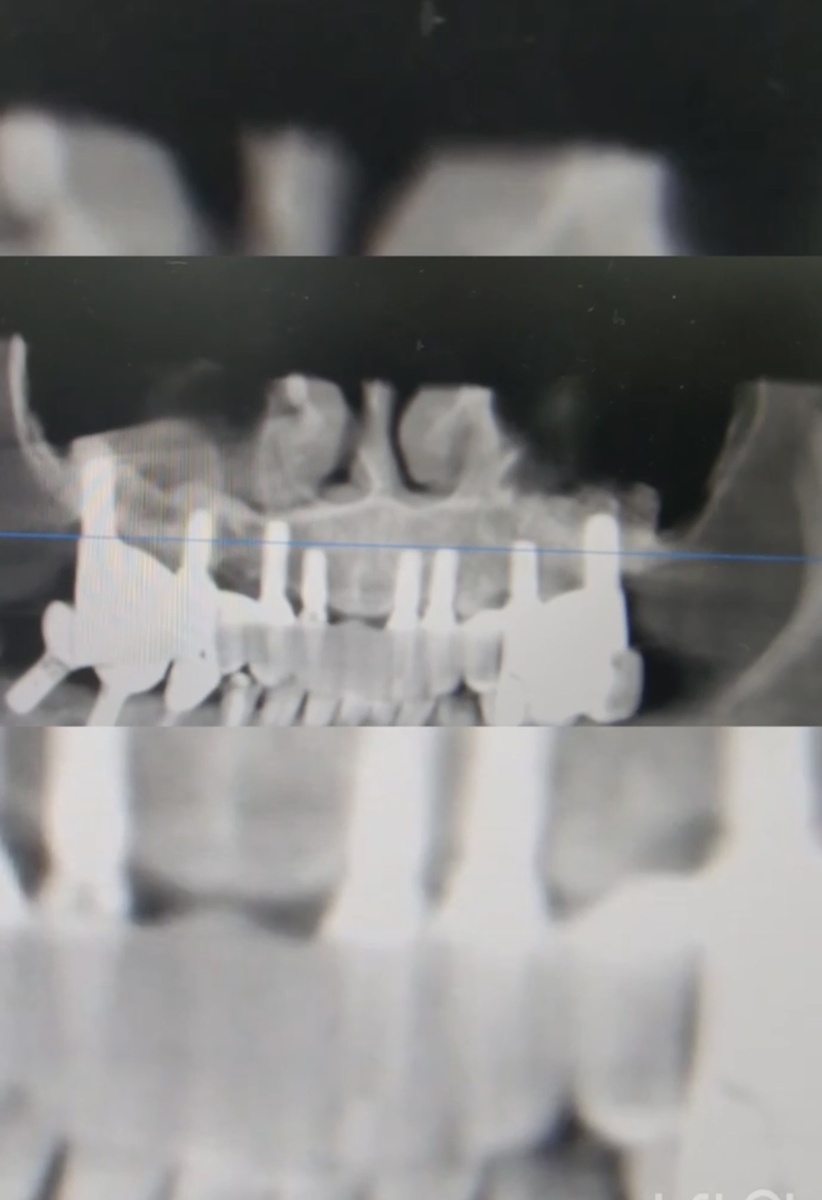

Тотальное протезирование верхней челюсти на имплантатах

Сегодня хотим рассказать вам об уникальном клиническом случае: пациент прошёл тотальное протезирование верхней челюсти на имплантатах и установку имплантов в области жевательных зубов нижней челюсти более 3-х лет назад. На последнем осмотре мы с радостью отметили стабильность и превосходное состояние как самих имплантатов, так и ортопедической конструкции.